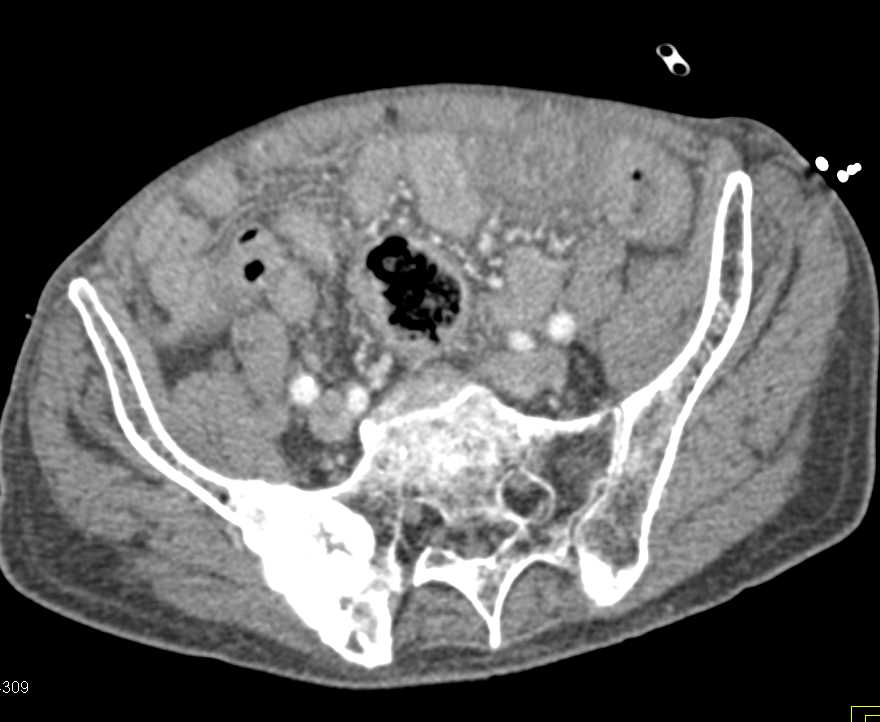

Dual Energy with Automatic Bone Removal